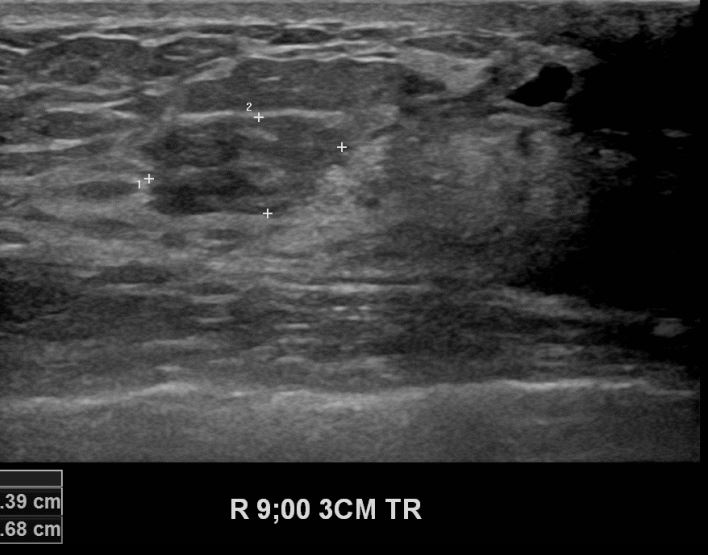

좌측유방에 만져지는 멍울있어 내원하신 30대 여성분으로 경과관찰중

우측유방의 자라는 혹이있어 조직검사 시행해 유방암 진단되셨읍니다